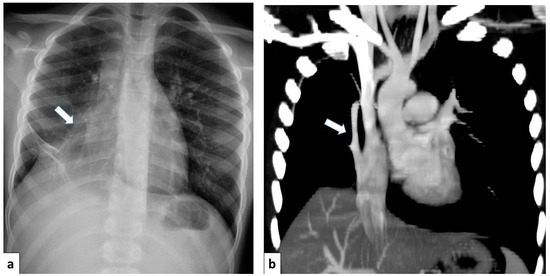

Pulmonary Arteriovenous Malformation